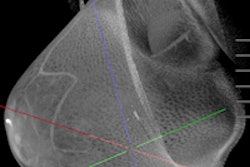

Koning said the deal with DocPanel will enable the remote reading of breast CT scans, which will help the growth and expansion of breast CT as an alternative to mammograms.